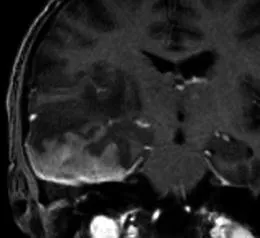

一名35岁头痛女性的造影后冠状T1加权序列显示,右中颅窝内有均匀增强的轴外质量,并有宽阔的硬脑膜尾(箭头)沿着蝶骨翼延伸,并围绕右额叶的侧面。肿块导致大脑镰下向左突出7毫米,右侧脑室消失。手术时的组织学结果为脑膜瘤(1级)

70岁头痛女性患者。增强冠状位T1加权序列显示右中央前回受压(箭头),病灶轻度不均匀强化,呈宽基底硬脑膜附着,周围显着血管源性水肿。T2加权序列呈高信号(相对于灰质)。术后病理证实为原发性乳腺癌腺癌转移。

63岁滤泡性淋巴瘤病史男性患者。增强冠状位T1加权序列显示右中颅窝轴外占位,宽基底硬脑膜附着伴硬脑膜增厚,并向轴内延伸至右颞叶。硬膜成分均匀强化,轴内成分轻度不均匀强化,周围水肿及占位效应明显。影像表现类似伴轴内侵犯的脑膜瘤,但病理确诊为淋巴瘤。